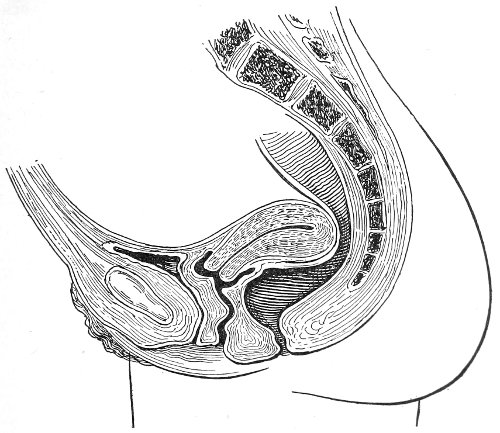

In making the bimanual examination the structures 25 should be palpated methodically in order. The vaginal finger notes the condition of the cervix uteri. If the fundus be in the normal position, the uterus can then be taken between the abdominal hand (upon the fundus) and the vaginal finger (upon the cervix) (Fig. 3). The shape, size, mobility, and consistency are noted. The vaginal finger is then passed anteriorly and laterally toward either uterine cornu, while the abdominal fingers pass over to the posterior aspect of the same cornu. The ovarian ligament and the proximal end of the Fallopian tube may thus be felt. Passing farther outward, the whole of the tube and the ovary may be examined. The same procedure is then applied to the opposite side.

Fig. 3.—Bimanual examination; median sagittal section of the pelvis.